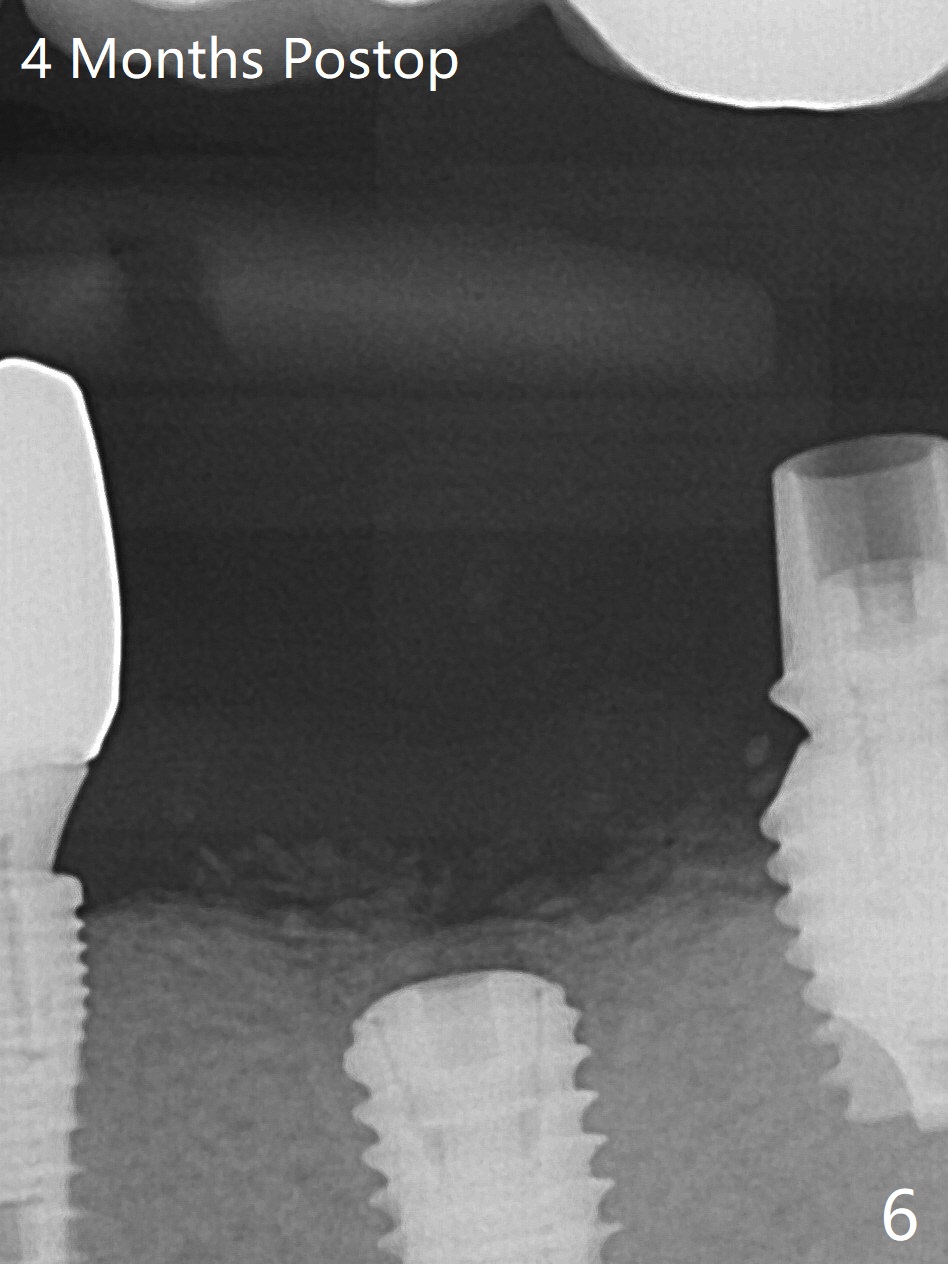

Since there is ~ 2 mm bone apical to the 5x8 mm loose implant at #19 (Fig.1), primary stability is achieved for a 4.5x10 mm dummy IS implant (having better surface treatment than the previous implant) when osteotomy is finished with a 4 mm drill (Fig.2). It is the same associated with a 4.5x7.3 mm definitive one with apical space (Fig.3 *). After depth adjustment to make sure that the implant is subcrestal circumferentially, sticky bone is placed on the top of the implant and around the implant at #18 (Fig.4 *), followed by PRF membranes and suturing with 5-0 PGA and 4-0 Chromic gut suture. Periodontal dressing is applied around the cemented abutment at #18 for additional retention. There is no paresthesia postop. In fact immediate implant redo is fairly safe. The wound heals 1 month postop (Fig.5). There is reorganized bone coronal to the healing screw 4 months postop (Fig.6), which is confirmed in uncovering. One month post uncover, the 6x4 mm healing abutment is found to be loose, suggesting incomplete seating after uncover. A 5.2x4.5(4) mm cemented abutment seems to be incompletely seated (Fig.7). It remains the same after 5.5 and 6.0 mm profile drills (Fig.8,9). A 4.5x4.5(4) mm abutment appears to be completely seated (Fig.10). When the crowns of #18 and 19 are cemented, the gingival embrasure between them is narrow (Fig.11 ^) because of bulky porcelain build-up (*). The tooth #21 with buccal Class V defect (Fig.12 *) seems to have occlusal trauma 1 year 6 months post cementation of #18 and 19. The problems are subsequently taken care of.